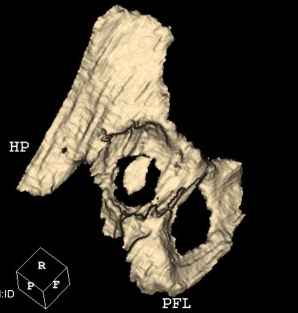

Мужчина, 45 лет. 6 мес. назад перенес тотальное эндопротезирование правого тазобедренного сустава по поводу ложного сустава шейки бедра.

Характер реконструкции вертлужной впадины не известен. Через 3 мес. после операции отметил щелчки и хруст при движениях в области эндопротеза. В анамнезе туберкулез легких. Сейчас, по заключению фтизиатра, в легких активного процесса нет. Местного воспаления нет.Предполагается нестабильность чашки в связи с бактериальным воспалением. Планируется удаление чашки и цемента, пластика дна измельченными аутотрансплантами и гидроксилапатитной керамикой, затем кольцо Мюллер, цементная чашка.

Смущает и ножка - зона просветления вокруг мантии. Предложения по тактике?

прямо скажем, очень загадочная конструкция с проволокой и винтами. :) На основании чего Вы подозреваете септическую нестабильность? Каковы результаты анализов? Согласен с доктором - нужно сделать пункцию. Есть ли снимки до и сразу после операции? Знаете ли Вы диаметр головки,какой будет внутренний диаметр Вашей чашки? Известно ли, чей протез? Может есть смысл найти автора работы и узнать о подробностях установки протеза?